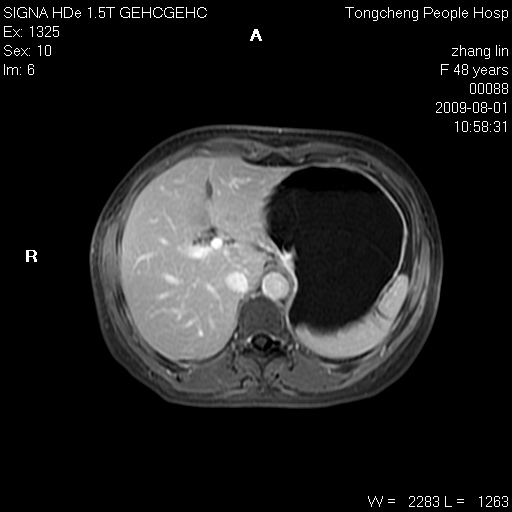

女,48岁。健康体检,彩超发现右肾占位性病变。平素健康。

临床诊断:右肾占位性病变,性质待定(囊肿?肿瘤?)。

上中腹部mr平扫+增强扫描,图像如下:

右肾上极见一类圆形病灶,t1wi呈等信号t2wi呈等高混杂信号,三期增强无强化,边界清---考虑囊肿出血。

同反相位均表现为等信号,病变无强化,考虑含蛋白的囊肿可能,弥散加权相或许有些帮助,

肝囊肿

慢性胆囊炎